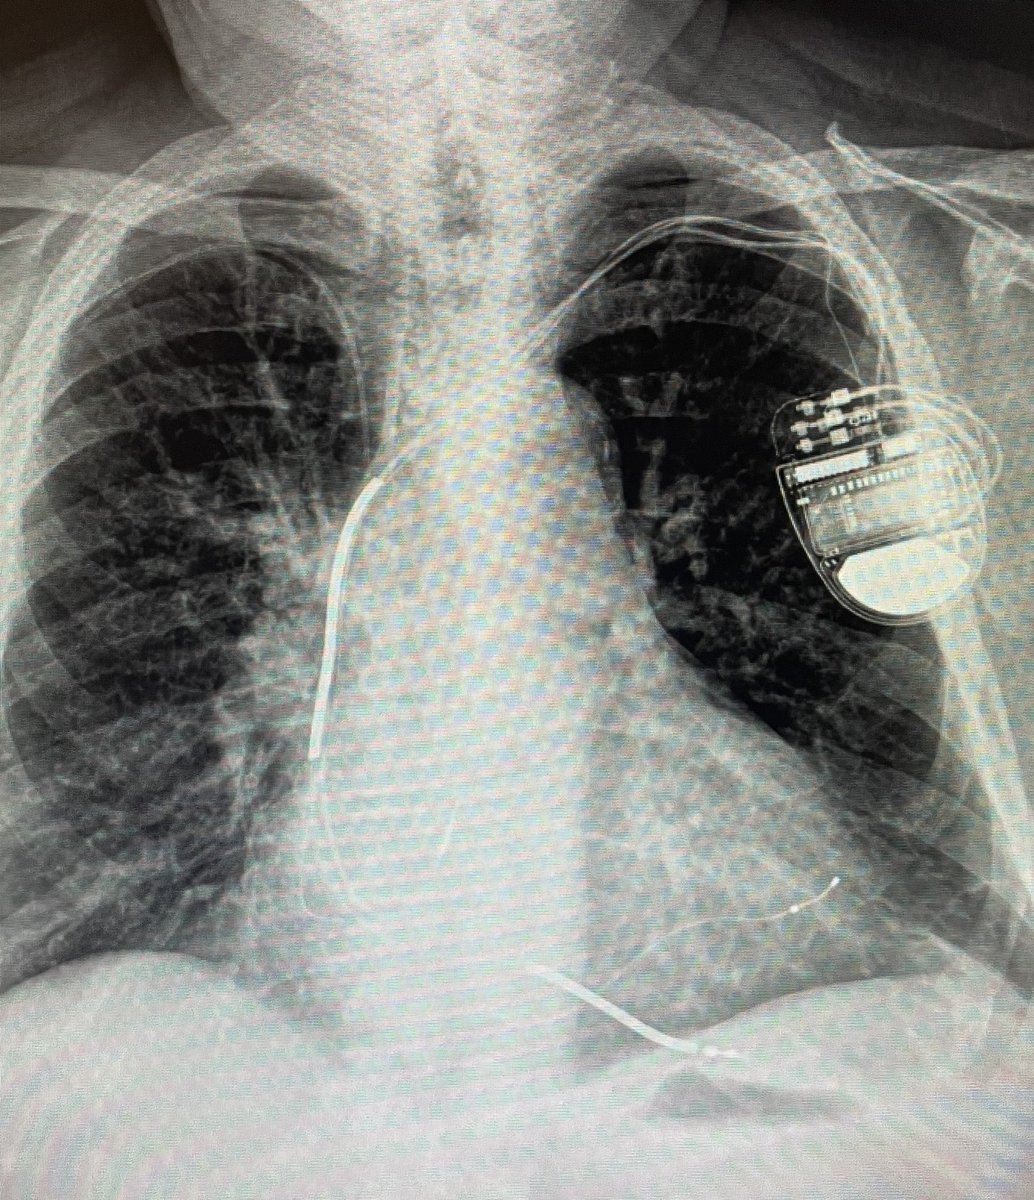

Bye bye anesthesiologists!…first S-ICD implanted only with local anesthesia in Chile!!!…at Hospital last Higueras Talcahuano…many thanks to @JorgeERomeroMD for his instrumental manuscript. @FellowEP @hhuang123 @DrRoderickTung @andresenriqueza @Yurgeny @BostonSciLatam